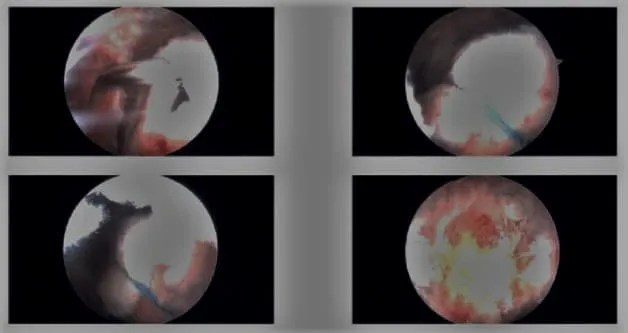

Imágenes artroscópicas intraoperatorias.

Un estudio reciente revisó las técnicas para mejorar la visualización durante la artroscopia de hombro, un procedimiento mínimamente invasivo habitual. La investigación destacó diversos factores que influyen en la visibilidad quirúrgica, como la posición del paciente (silla de playa frente a decúbito lateral), el control de la tensión arterial y la gestión de líquidos con bombas artroscópicas.

En particular, se observó que el uso de epinefrina (EPI) y ácido tranexámico (TXA) en el líquido de irrigación mejoraba significativamente la claridad visual. La EPI actúa como vasoconstrictor, reduciendo la hemorragia, mientras que el TXA impide la fibrinólisis, lo que contribuye a mejorar la visualización y reducir las complicaciones postoperatorias.

El estudio concluyó que estas medidas, junto con un posicionamiento cuidadoso, desempeñan un papel fundamental en la optimización del entorno quirúrgico, mejorando potencialmente los resultados y reduciendo las complicaciones. («Estudio sobre la artroscopia de hombro – ver PubMed.»)